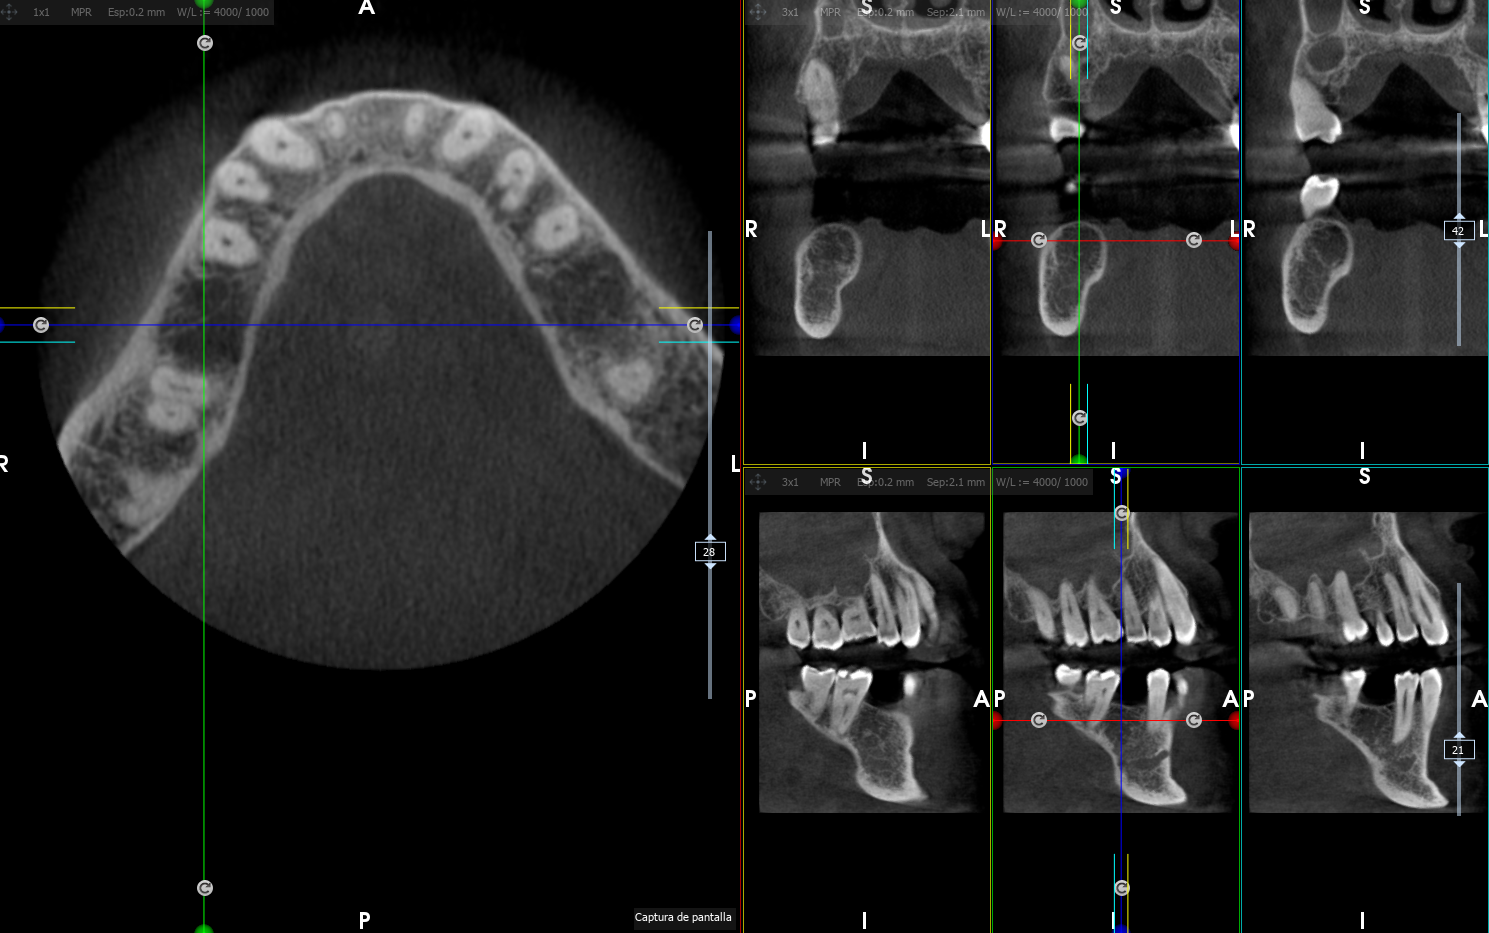

En Clínica Hervás disponemos de TAC dental para la obtención de imágenes 3D tanto de dientes como del maxilar y la mandíbula. Esta es una herramienta imprescindible en la odontología actual, sobretodo en el estudio para la colocación de implantes.

Si no eres paciente de nuestra clínica pero en tu dentista te han solicitado hacerte un TAC para evaluar el estado de tu hueso, podemos realizarte aquí el TAC y enviarlo a tu odontólogo para que pueda estudiarlo.